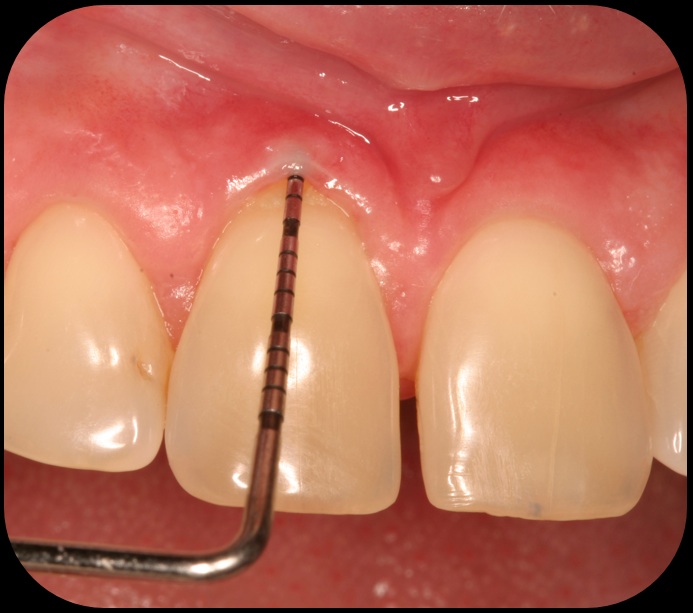

Severe periodontitis lesion.

Fig. 2

Then, too, are opportunities to prepare the site for regeneration by coupling therapies, applying an enamel matrix derivative, along with traditional bone grafts of demineralized freeze-dried bone allograft; potentially, gains in attachment with minimal probing depth and retained papilla may avoid the need for an implant (Figure 2 through Figure 7).